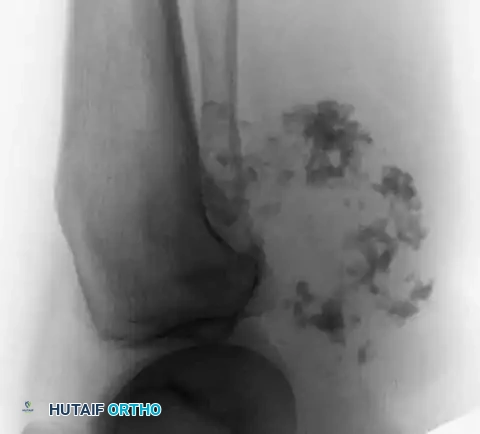

Image

Fig. 22-7 B: A catastrophic failure of treatment. Malignant features were not recognized by the referring surgeon, who performed a simple curettage followed by iliac crest bone grafting without extended margins or adjuvants, leading to massive local recurrence.